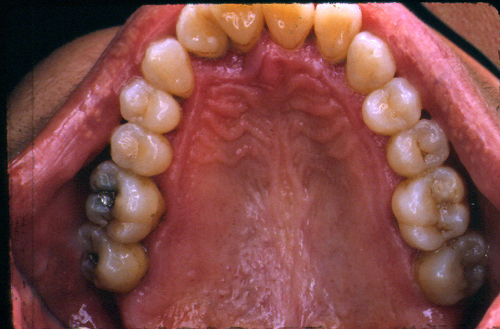

INTRODUCCION La rehabilitación oral como especialidad multidisciplinaria, obliga al profesional a pensar en términos complejos, donde la observación de todos y cada uno de los elementos constituyentes del sistema Estomatognático se hace imprescindible para el arribo a un diagnóstico de certeza. Sabido es que el esmalte dentario se desgasta con el correr de los años. Sin embargo, es importante determinar como se produce dicho desgaste y si éste responde a una cuestión de carácter fisiológico o se trata de una manifestación patológica. Adaptativas Tienen paca velocidad de desgaste. Su localización es exclusivamente de esmalte. No hay deformación oclusal y se producen cuando el sistema neuromuscular es aún inmaduro. Madurativas En la oclusión adulta los contactos interoclusales son puntiformes, ya que contactan convexidades contra convexidades. Parafuncionales Son las únicas que podemos considerar patológicas. Su velocidad de desgaste es mucho mayor y se localizan en dentina, pudiendo o no ser sintomáticas. En los anteriores el desgaste puede ser plano y parejo, lo que significa que el paciente bruxa en sentido anteroposterior. Si por el contrario, el desgaste es curvo, el bruxismo es de carácter latero-lateral. En los posteriores podemos observar en casos avanzados que las cúspides estampadoras presentan una facetamiento mayor que las cúspides de corte, ya que en las lateralidades aquéllos que rozan el doble de veces que éstas últimas, dando lugar al llamado desgaste “en olla” e invirtiendo la curva de Wilson. MATERIAL Y MÉTODOS En el desarrollo de este trabajo se utilizaron onlays de oro (Ventura 120). CASO CLÍNICO El paciente se presenta a la consulta derivado y con severas mialgias difusas y referidas fundamentalmente a la cara, región posterior del cuello y ocasionalmente en la región occipital y temporal. Mujer 55 años, prácticamente sin historia odontológica anterior, ya que dice tener una dentadura excelente y que sólo visita a su dentista con relativa periodicidad para limpiezas, ya que caries cree no tener. Se evidencian signos depresivos cuando manifiesta que no sabe como dar solución a su problema. El examen periodontal denota bolsas poco profundas salvo en el incisivo superior lateral izquierdo, que también ofrece una moderada movilidad y ligeramente vestibulizado. El examen de la ATM determina la presencia de ruidos articulares en apertura y cierre y dolor a la palpación. Durante este examen manifiesta haber tenido dificultades para la apertura en reiteradas ocasiones. Fig 1/2 Se toman modelos de estudio y se duplican. Antes de proceder a su correspondiente montaje en un articulador semiajustable, se observan individualmente cada uno de3 ellos haciéndose ya objetiva la presencia de facetas de desgaste que, sin duda, tienen un origen y que nos darán la clave de nuestro diagnóstico (Fig. 3). Montados ya los modelos en oclusión en relación céntrica, mediante el que considero el más fisiológico medio de obtención de la misma: las laminillas de Long, preconizado por el Dr. W.H. McHorris (*), y que nos permite romper con los engramas o patrones de memoria muscular que trae el paciente y que en muchos casos, como éste, llevan a la mandíbula fuera de su posición esqueletal fisiológica, y que la obliga a trabajar en medio de contracturas musculares fundamentalmente del pterigoideo Externo. Cabe en este punto recalcar que es la ORC la única posición diagnóstica posible, la que, además de permitirnos obtener el eje de bisagra Terminal, es la única posición repetible. Al mirar los modelos montados según estos conceptos, podemos ver un punto prematuro de contacto (contacto único) (Fig. 4) Llevamos entonces la rama inferior de nuestro articulador hacia la posición a que dicho punto la guía, alcanzando la oclusión habitual (OH) en la que el paciente desarrolla su masticación. Podemos ver entonces la migración que dicho maxilar realiza hacia delante y a la izquierda, produciéndose una discrepancia horizontal. Dicha discrepancia obliga a la permanente contractura del pterigoideo externo del lado opuesto y el consecuente encadenamiento de pequeñas contracturas entre los músculos protagonistas, antagonistas y agonistas que rigen el movimiento. Procedemos a realizar el ajuste oclusal en el articulador mediante sustracción y adición, anotando prolijamente la secuencia del mismo, obteniendo así un único arco de cierre: ARCO DE CIERRE TERMINAL DE BISAGRA; y logrando mediante composites en las desgastadas puntas caninas, una disclusión canina (oclusión mutuamente protegida). Transferimos nuestro primer desgaste a la boca e instalamos la placa. Una semana después de uso nocturno pedimos al paciente que regrese, permaneciendo la placa en posición desde unas horas antes de la consulta, y observamos la enorme destalación que experimenta la mandíbula. Hacemos entonces un nuevo ajuste de la oclusión en boca. Adicionamos más composite a los caninos, tal como antes lo habíamos hecho con cera en el articulador. En este punto del proceso, vinculando ya la sintomatología con la discrepancia, evaluamos si la estabilidad oclusal será permanente o no. Al observar que los contactos son de superficie contra superficie, donde las fuerzas de deslizamiento se transforman en fuerzas de rozamiento (factor de alto potencial patológico) decidimos reestructurar la morfología oclusal para finalmente obtener los cuatro pilares fundamentales de la oclusión orgánica: AXIALIDAD, ESTABILIDAD, NO INTERFERENCIA, Y ALINEACIÓN TRIDIMENSIONAL. Considerando la edad de la paciente, sus escasas exigencias estéticas y el valor otorgado por la misma a la recuperación ad integrum de sus funciones, optamos por el oro como material óptimo de elección. Procedemos entonces a realizar sobre nuevos modelos de trabajo, con guía anterior ya modificada, un encerado de las tablas oclusales premolar-molar mediante el método de encerado progresivo de Meter K. Thomas. Obtenemos réplicas en yeso de este encerado y lo estampamos obteniendo así una matriz que reproduce las caras oclusales previamente diseñadas, este estampado luego nos servirá para obtener un juego de provisionales de metacrilato, según nuestra primera concepción de la morfología oclusal necesaria para obtener Estabilidad y Alineación Tridimensional, ya que los otros dos pilares fueron obtenidos: Axialidad al obtener un único arco de cierre, y No Interferencia con la modificación de la guía anterior. (Fig. 5/6). Construimos los provisionales a partir del estampado, lubricando previamente los muñones con una crema de corticoides para contrarrestar los efectos inflamatorios del metacrilato, y los cementamos con un producto a base de hidróxido de calcio, previa comprobación en el articulador de que se cumplen con los mismos todos los conceptos proyectados. En las siguientes dos semanas , durante las cuales la paciente sigue durmiendo con la placa de relajación colocada, seguimos ajustando la oclusión observando que la mandíbula prosigue aún más su distalación. Esperamos el período de tiempo necesario para que se estabilice una posición, la que consideramos la ORC mas adecuada y entonces procedemos a determinar el eje de bisagra Terminal ya con mucha más precisión por medio del localizador de eje de bisagra de Almore. Montamos entonces los modelos de trabajo; realizamos un nuevo encerado progresivo y colamos. (FIG. 7/8) Buscamos en el encerado, como lo hicimos ya con el encerado provisional, los puntos de contacto interoclusales: Sttoper y Equalitzer, como así también los puntos A, B y C, que nos otorgarán la estabilidad adecuada y comprobamos su presencia en los colados. Volvemos a instalar y comprobamos las correspondientes disclusiones y la presencia de un único arco de cierre, datos con los cuales hemos logrado eliminar la discrepancia que originó la sintomatología. Por fin bruñimos los bordes cavo superficiales de las restauraciones y cementamos alternadamente para permitir la mejor eliminación de los restos de cemento. Realizamos los primeros controles a la semana, al mes ly a los seis meses. Los síntomas no han vuelto a presentarse y la salud individual de cada pieza dentaria implicada es completamente normal. DISCUSIÓN Diversas son las escuelas que persiguen el logro de la estabilidad una vez obtenida la salud integral de todos los componentes del SEG. Las principales líneas Harvey Stallard, Charles Stuart, Meter K Thomas, Lucía, y más actualmente, y más actualmente, pensamientos tan claros y contemporáneos como los de W.H. McHorris, Sumiya Hobo, Axel Bauer, Aníbal Alonso, Echeverri Guzmán, etc., conllevan a crear una Odontología estrictamente científica, como así también equilibradamente artística. El logro de contacto puntuales y tripódicos, la génesis de puntos Sttoper y Equalitzer (topes y estabilizadores) para la obtención de una estabilidad mesio-distal, y de puntos A, B y C para la estabilidad vestíbulo-lingual, muestran bien a las claras que la estabilidad es lograble. Presentación de un caso clínico donde pudieron ponerse en práctica todos los conceptos inherentes a la rehabilitación gnatológica con fines de resolución de sintomatología diversa, como mialgias difusas, desviación de la línea media mandibular, ruidos articulares en apertura y cierre, etc., haciéndose hincapié en el valor diagnóstico de la presencia de facetas para funcionales de desgaste. La documentación fotográfica del caso cuenta con alrededor de doscientas diapositivas. BIBLIOGRAFÍA 1 McHorris WH. La Disfunción de la Articulación Temporomandibular. Resolución antes de la reconstrucción 6ª Conferencia Gnatológica Internacional.. México 1973. BIBLIOGRAFÍA COMPLEMENTARIA 1 McHorris WH. Relación Céntrica. Memphis, Tennesse USA. 1977.

Este es el momento de abordar clínicamente el caso, procediendo a los tallados según los conceptos de la gnatología y impresionar los mismos

Instalamos en boca y realizamos un proceso de remonta. Volvemos a montar y ajustamos en el articulador los puntos necesarios.

RESULTADO